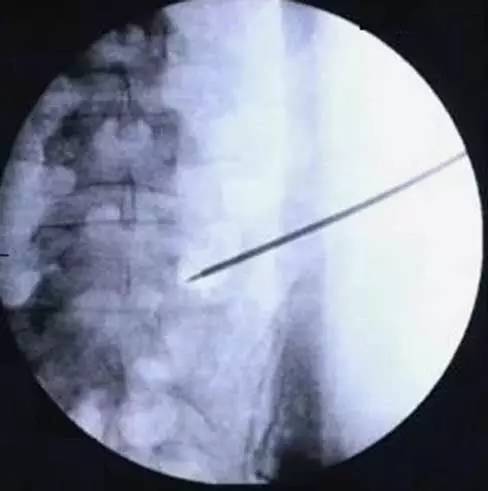

第三步:置入导丝

穿刺点以 1% 利多卡因 2~3 mL 行局部麻醉,然后穿入 18 G 穿刺针并以 1% 利多卡因 8~10 mL 麻醉穿刺路径。在侧位片上,穿刺针与头尾方向呈 55~65°角;在正位片和轴面观(C 臂无法获得该平面影像)应与后前方向呈 30~40°角。

穿刺针尖到达上关节突后,用 1% 利多卡因 2~3 mL 麻醉关节面(注意利多卡因不要给的太多,否则很可能麻醉神经根,使患者对神经根刺激失去反应)。通过穿刺针置入导丝并移去穿刺针。随后以空心锥形套管将手术入路逐级扩大至 8 mm。(图 6,7)

图 6 以 18 G 穿刺针于 L5/S1 节段穿刺并置入导丝